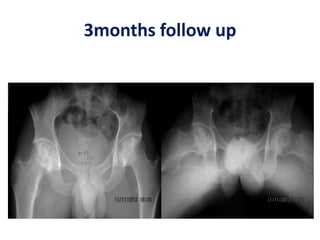

3months follow up

Case 5- hips8,9 – 6 weeks